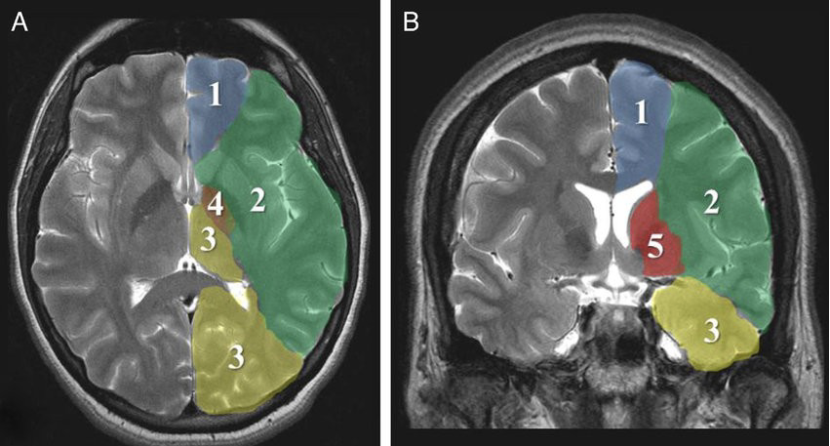

Supply areas of the cerebral arteries. A: axial slice; B: coronal slice. (1) Anterior cerebral artery, (2) middle cerebral artery, (3) posterior cerebral artery, (4) anterior choroidal artery, (5) lenticulostriate arteries.